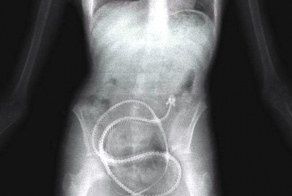

- Необычные вещи, найденные в человеческом желудке